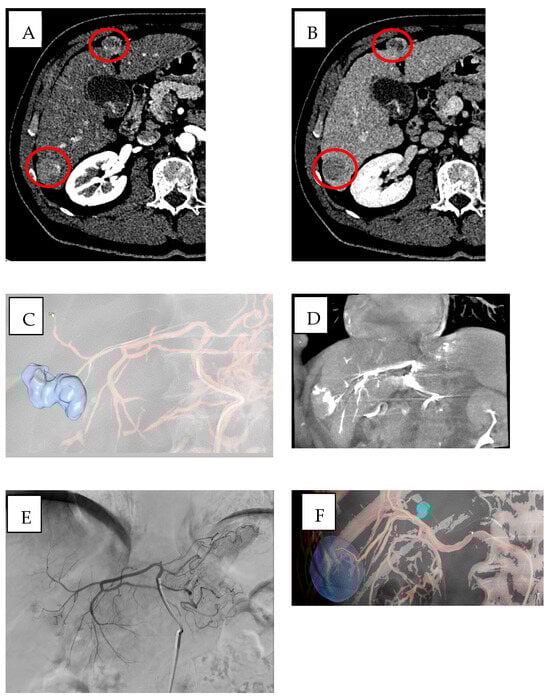

In vascular procedures, CBCT can be used in addition to automated tumor feeder detection [] to improve both safety and precision of embolization therapies. The AFD systems, achieving real-time 3D visualization of blood vessels through advanced imaging techniques with intelligent algorithms [,], consisting in three steps, in which the first step is the manual identification and segmentation of a ROI, the second is the manual identification of tip of catheter, and finally the last step is the automated identification of feeding arteries. The final 3D roadmap, containing the segmented ROI and feeding arteries and the paths from catheter to vessels, has been overlaid onto the live fluoroscopy images [] (Figure 2).

Figure 2.

Multifocal HCC in a patient with HBV/HDV/alcohol-related cirrhosis (BCLC stage B) treated with DEB-TACE using BioPearl (Tokyo, Japan). (A,B) Pre-treatment CT shows two subcapsular lesions (~3 cm) in segments VI and IV with (A) arterial hyperenhancement and (B) venous washout (red circles), consistent with HCC. (C,D) Emboguide (Version 1.2.1, Philips) software and CBCT mapping of the arterial pathway from the right hepatic artery to the target lesion in segment IV. (E) Angiographic image showing the lesion in segment IV supplied by the left hepatic artery. (F,G) Emboguide (Philips) software and CBCT mapping of the right hepatic artery pathway to the lesion in segment VI before chemoembolization, showing enhancement of the target area. (H,I) Post-treatment CT in (H) arterial and (I) venous phases demonstrates hypodense areas (~3.5 cm) in segments VI and IV, consistent with treated lesions (red arrows).

These software utilize dynamic contrast-enhanced imaging for peak vessel visualization which enhances vascular structure definition, especially when dealing with tumors displaying irregular or abnormal blood supply. Real-time integration of these images enables precise catheter navigation which supports embolization procedures with reduced requirements for extensive fluoroscopy exposure [,].